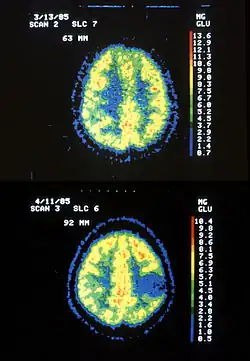

| Two PET images—the upper of which shows a normal brain and the lower shows astrocytoma | |